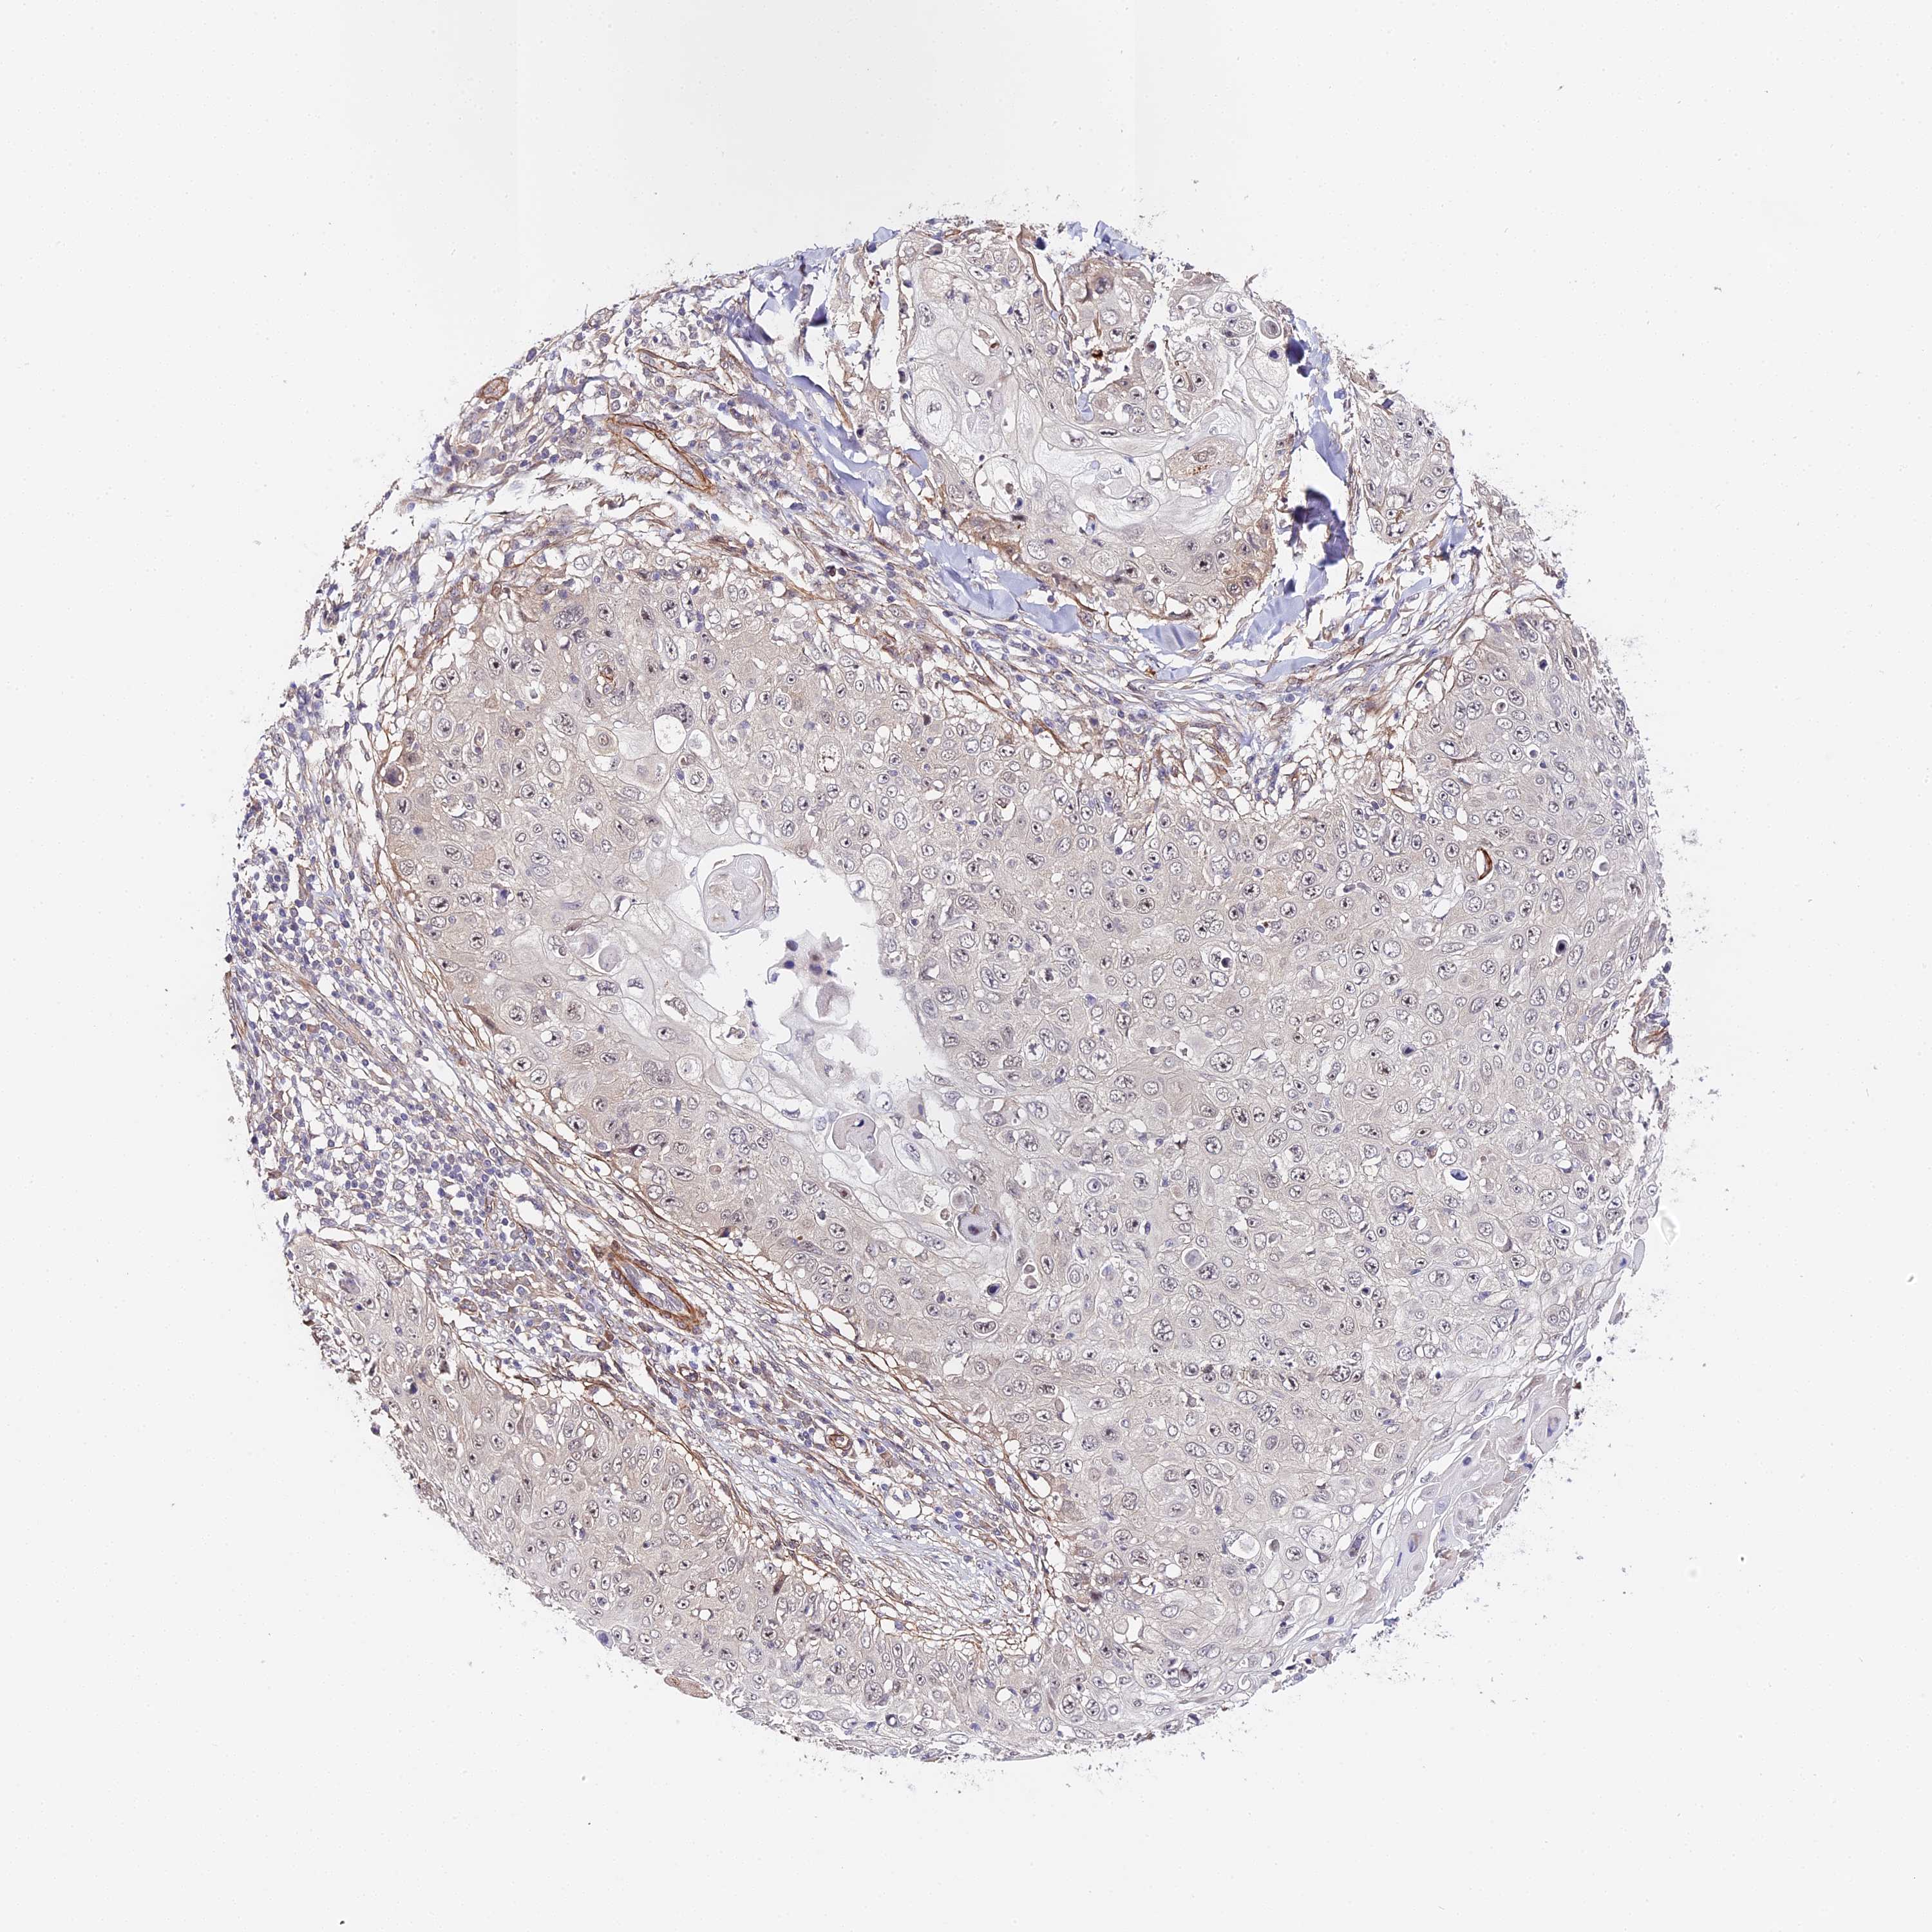

SKIN CANCER - Protein expressioni

A mouse-over function shows sample information and annotation data. Click on an image to view it in a full screen mode. Samples can be filtered based on level of antibody staining by selecting one or several of the following categories: high, medium, low and not detected. The assay and annotation is described here.

Antibody stainingi

Antibody staining in the annotated cell types in the current human tissue is reported as not detected, low, medium, or high, based on conventional immunohistochemistry profiling in selected tissues. This score is based on the combination of the staining intensity and fraction of stained cells.

Each image is clickable and will lead to virtual microscopy that enables deeper exploration of all samples and also displays staining intensity scores, fraction scores and subcellular localization as well as patient and tissue information for each sample.

Antibody HPA041045

Antibody HPA041968

Squamous cell carcinoma, NOS

Basal cell carcinoma